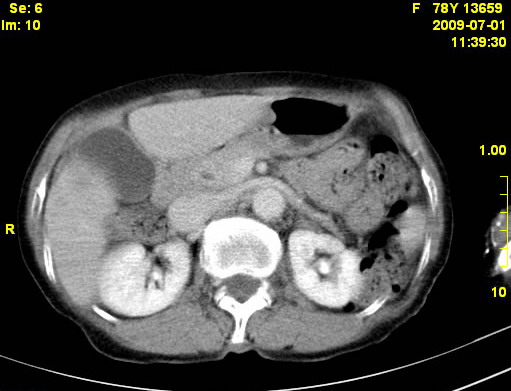

以下是引用zjzjr在2009-7-3 11:02:00的发言:[br]动脉期不均匀强化,门脉期及延迟期强化明显,肝门部见肿大淋巴结影,肝内胆管扩张.考虑肝右叶前段胆管细胞癌伴肝门淋巴结转移,胆内胆管扩张.慢性胆囊炎.

以下是引用dsl555在2009-7-4 10:59:00的发言:[br]考虑肝右叶前段胆管细胞癌伴肝门淋巴结转移,胆内胆管扩张.慢性胆囊炎. [br][br]支持。